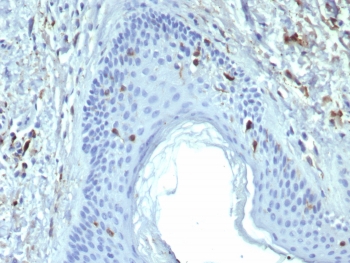

IHC staining of FFPE human skin tissue with Langerin antibody (clone LGRN/7428). HIER: boil tissue sections in pH 9 10mM Tris with 1mM EDTA for 20 min and allow to cool before testing.